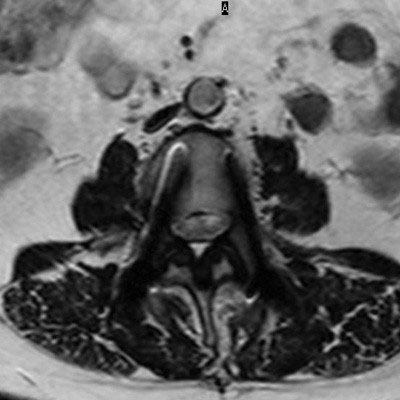

Lumbar Spine with metal implant, routine and fast

Utrecht Medical Center, The Netherlands

**Only for use with MR Safe or MR Conditional Implants by strictly following the Instructions for Use.